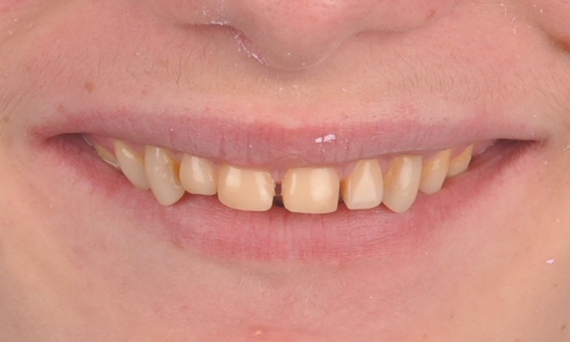

Before: Clinical Situation pre-op. Trauma of upper central incisors

After: Adhesively bonded restorations.

Minimal Preparation Veneers after Trauma of Upper Central Incisors

Restoration with a highly esthetic material in one day after trauma to the maxillary central incisors.